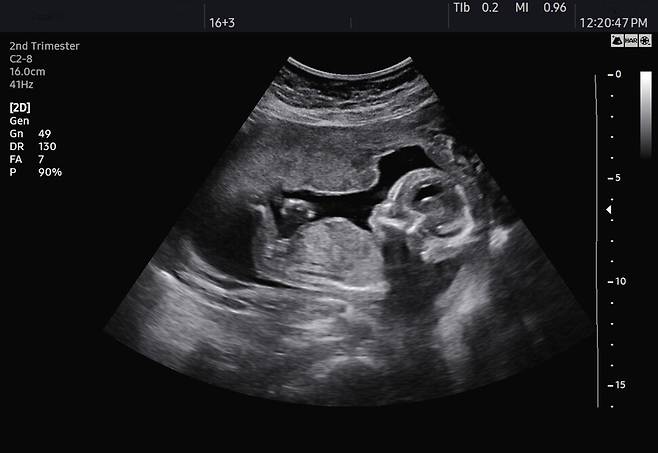

아빠 노동자의 유해한 작업환경과 자녀의 선천성 질병 사이에 ‘업무 관련성’이 있다는 근로복지공단의 첫 판단이 나왔다. 그러나 현행법이 엄마가 아닌 아빠 노동자의 ‘태아산재’는 보상 대상으로 삼지 않고 있어, 자녀 치료를 위한 요양급여 신청은 승인되지 못했다.

정씨는 2004년부터 2년 동안 삼성전자 엘시디(LCD)사업부 탕정사업장에서 안전보건 업무를 담당했고, 아내의 아이 임신을 전후해서는 삼성전자 천안사업장에서 박막트랜지스터(TFT) 자동광학검사 설비 유지·보수 엔지니어로 일했다. 2008년 5월 태어난 아들은 눈·귀·심장 등에 유전성 기형이 나타나는 ‘차지증후군’ 진단을 받았다. 정씨의 아들은 왼쪽 눈과 귀에 장애가 생겼고, 발달도 또래보다 느린 상황이다.

공단은 정씨가 과거 맡았던 업무와 아들의 질병 사이에 관련성이 있다고 판단했다. 아빠 ‘태아 산재’의 업무 관련성이 인정된 것은 이번이 처음이다. 공단 서울남부업무상질병판정위원회는 “전자산업종사 남성의 2세에서 선천성 기형 및 선천성 기형의 빈도가 높아지고 있는 점과 정씨의 과거 근무 시기, 근무라인을 고려하면 독성물질 노출이 현재 역학조사의 기준보다 더 높았을 것으로 판단된다”며 “자녀의 차지증후군은 정씨 업무와의 상당인과관계가 인정된다”고 봤다.

그럼에도 아들의 치료를 위한 요양급여 신청이 승인되지 못한 것은 산재보험법의 미비 때문이다. 지난해 1월부터 시행된 개정 산재보험법은 “임신 중인 노동자가 업무수행 과정에서 유해인자의 취급이나 노출로 인하여, 출산한 자녀에게 부상, 질병 또는 장해가 발생하거나 그 자녀가 사망한 경우 업무상의 재해로 본다”고 규정한다. 이에 따라 간호사 자녀의 선천성 뇌 기형 질환이 업무상 재해로 인정되는 등 엄마의 ‘태아 산재’에 대한 보상이 이뤄지고 있다. 그러나 아빠는 ‘임신 중인 노동자’에 해당하지 않아 정씨처럼 불승인이라는 결론에 이르게 된 것이다.